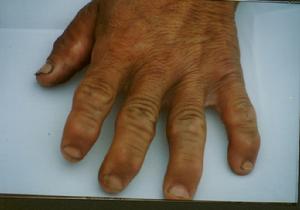

關節增粗變形多見於手(指)、足(趾)間關節、掌指關節,逐漸發展到腕、肘、膝關節,晚期重症病人肩關節和髖關節受累。常先出現在第2、3、4指的第1指間關節,以近位指間關節最為明顯,由於指骨關節端變扁平和向外膨大,而致關節隆起。踝關節增粗、變性,在早期檢出率相當高,僅低於指關節,踝關節增粗常伴有足跟外形臃腫、足弓扁平畸形。少數病人在指關節增粗前,先出現肘關節彎曲,左右肘關節彎曲程度常不相同。膝關節亦可出現增粗、變性。關節增粗呈多發性、對稱性。受累關節部位的皮膚和軟組織無發紅、腫脹等改變,也很少有壓痛。關節摩擦音:從細小捻發音到粗糙的摩擦音不等。

大骨節病

輕度以上患者四肢肌肉特別是手掌大、小魚際肌、上臂肱二頭肌、肱三頭肌及小腿腓腸肌可見肌萎縮,這種現象在關節有明顯改變之前就可出現。

增粗關節活動範圍變小,關節活動受限。肘關節屈伸受限,彎曲呈挎筐狀;肩關節受累;膝關節內翻或外翻,出現下蹲困難,直立曲膝,代償性腰椎前彎,臀部後突,扁平足。嚴重者腳步掌狀如熊掌,此時病人步態搖擺,即所謂的“鴨步”。踝關節跖屈和背伸障礙。

嚴重病人出現手指、足趾與年齡身高不符,明顯短縮,有時伴有關節半脫位,手指向尺側或橈側彎曲,即所謂的短指(趾)畸型。四肢與頭和軀幹相比表現為勻稱短縮,上臂與前臂相比特別短,手指不能觸及大轉子;脛腓骨短,與肱骨及軀幹相比不成比例。因此病人坐如常人高,立起則矮半截,呈矮小畸型。病人因關節增粗變形,運動障礙和疼痛,勞動能力下降,甚至完全喪失勞動能力,至生活不能自理。